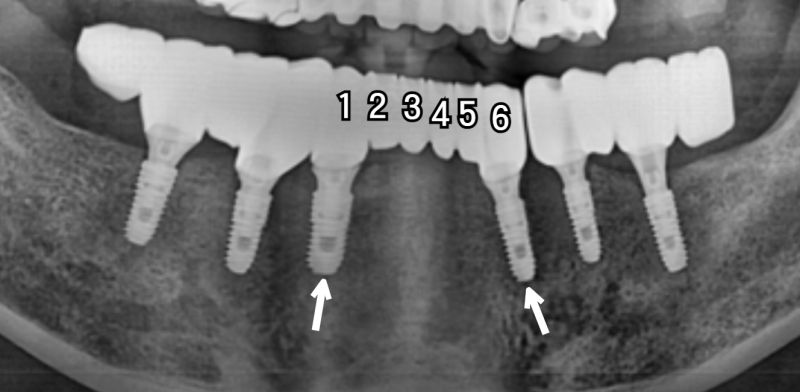

안산치과 – 치아가 6개 상실되었다면?

치아가 6개나 상실되었다면.. 아마 많은 걱정을 하실 텐데요. 그러나 이 경우에도 마찬가지로 ‘브릿지’ 형태를 활용하여 6개보다 더 적은 개수만 심는 경우가 많습니다.

예를 들어 전치부(앞니 2개와 송곳니 1개)는, 씹는 힘이 어금니만큼 강력하지 않습니다.

따라서 위 사진처럼, 픽스쳐는 2개만 심고 브릿지 형태로 치아 6개 역할을 할 수 있습니다.

만약 앞니가 아니라 어금니 쪽에 4 ~ 5개 이상 상실되었다면, 마찬가지로 위 사진처럼 브릿지 형태로 연결하여 임플란트 식립 개수를 줄일 수 있습니다.